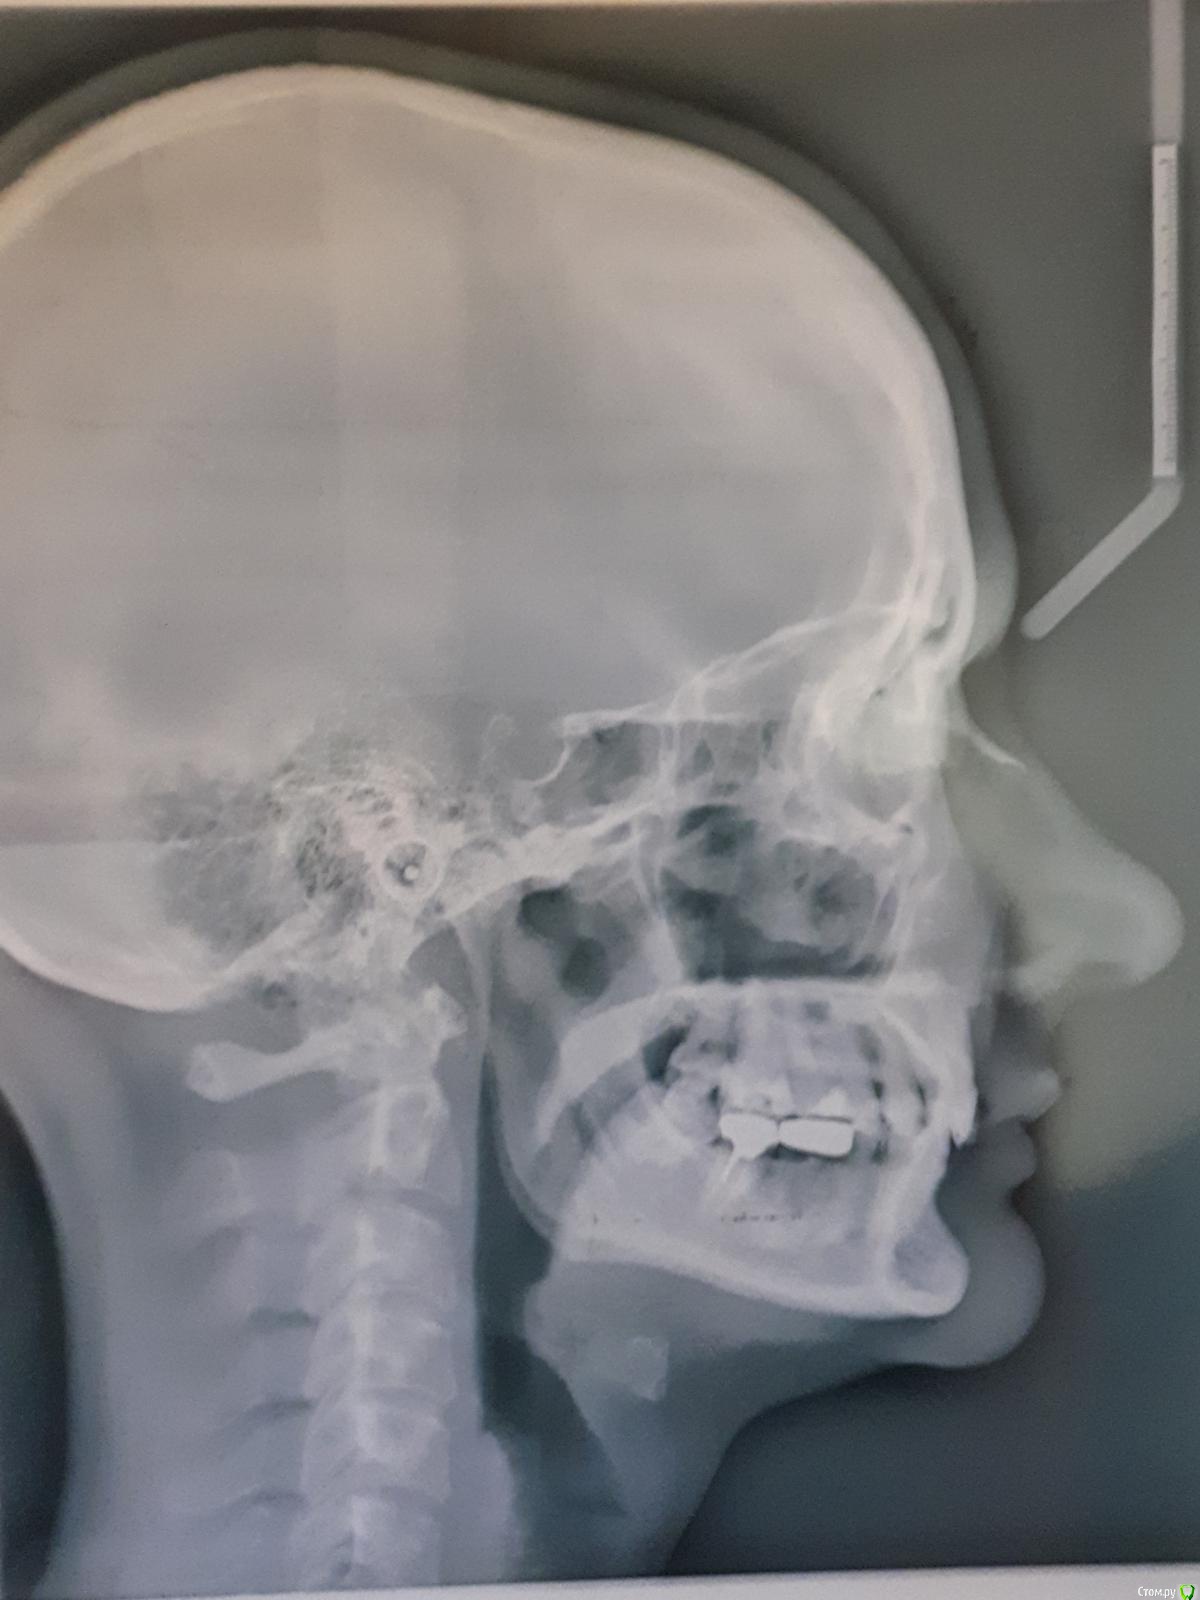

Thunder Опубликовано 17 октября, 2019 Поделиться Опубликовано 17 октября, 2019 Приветствую всехПрошу быть снисходительными: рассказываю свою историю первый раз, заранее приношу извинения за возможный сумбур и некорректность в использовании проф. терминологии. Мне 40 лет. У меня:-глубокий прикус-скученность зубов во фронтальном отделе в/ч и н/ч; -короткая уздечка верхней губы, -мелкое преддверие полости рта, -тонкий биотип пародонта; -проблемы с суставом (левым), который периодически дает о себе знать: обычно ограничивается щелканьем, но пару раз и воспалялся (боли, рот с трудом открывался, особенно по утрам). Ничего, кроме местных мазей на сустав не наносила и особенно им никогда не занималась.- В этом году мне поставили диагноз полиостеоартроз (болят суставы нижних конечностей). - постепенно появился перекос челюсти влево, видно уже невооруженным глазом (возможно, после удаления верхней левой восьмерки)Прикус никогда не исправляла, по разным причинам, в том числе, потому что не хотела ставить брекеты. И сейчас не хочу (комплексы). Комплексы от некрасивой улыбки тоже были, но к своей внешности за столько лет уже привыкла (и смирилась), кроме того она мне совершенно не мешала жить. Однако!В последние годы вынесла основную мысль от стоматологов – мои суставы разрушаются (в большей степени левый), происходит это из-за моего прикуса, который срочно надо исправлять. Эстетика лица для меня – вторична. Вся работа над зубами должна проводиться именно для сохранения сустава (ну и чтобы зубы не потерять).В начале 2019 г. были сделаны ОПТГ, КТ и ТРГ. Есть еще зонография ВНЧС (правда от 2017г.) // не поняла, как КТ подгрузить, но есть описание врача Пикассо. Если надо будет, просто загружу как текст. Остальные фото, надеюсь, подгрузить получится// По КТ ортодонт, к которому я, наконец, обратилась, выявил «убыль костной ткани межальвеолярных гребней и вестибулооральных стенок по смешаному типу до 2,0 мм.» (кортикальная пластинка истончена по вестибулярной поверхности на передних зубах (в/ч зубы 1.2-1.1,2.1-2.4; н/ч зубы 3.1.-3.4, 4.1-4.5) до 0,1 мм). Мой ортодонт (лечение на капах) сказала, что риск потерять зубы при лечении на капах – 50/50, при лечении на брекетах – и того выше. После этого, конечно, я ушла.Стала искать дальше. Каждый раз мнения разнились:1 вариант: можно капами исправить прикус, но крайне осторожно2 вариант: только (!) брекеты. Тема потери зубов обходится стороной или уверяют, чтобы зубы останутся на месте засчет длинных корней. Если я не поставлю брекеты притом срочно – через несколько лет я потеряю все зубы, и мне придется тратиться на съемные протезы3 вариант: зубы вообще не трогать, просто всю жизнь носить каппу, помогающую моему суставу.4 вариант (стоит особняком): суставная каппа на нижнюю челюсть + одновременно аппарат ALF на верхнюю.Почему ALF? потому что из всех ортодонтических аппаратов для исправления прикуса этот – самый щадящий. Брекеты категорически не рекомендованы, потому что самые агрессивные по воздействию, каппы дороже + отмели из-за сустава: его было удобнее лечить параллельно с ALF. Смысл использования у меня ALF (как поняла) не столько в расширении челюсти, сколь в изменении наклона верхних зубов, которые не «пускают» нижнюю челюсть вперед. Мои зубы при этом не выпадут, а врастут в кость, изменив угол наклона.Второй этап – ALF или инвизилайн на нижнюю челюсть; и для возобновления смыкания боковых зубов – пломбы или коронки (эта часть смутила). В данном лечебном плане было прекрасно все, кроме моей неуверенности в достаточной квалификации врача. У меня сложилось впечатление, что для врача эта методика как бы.. далеко не основная. Она использует ALF просто как один из вариантов ортодонтических аппаратов (наряду с брекетами и пр.), а я так понимаю, у ALF философия немного другая (тесная связь с осанкой, остеопатией и пр.) – хотя могу и ошибаться. И в принципе эта методика новая, не особенно опробованная в России, отзывов нет, особенного опыта у врачей тоже. Страшно.Мучают вопросы, на которые здесь, возможно, получу ответы:1. мне были рекомендованы френулопластика на в/ч, вестибулопластика на н/ч. На сколько это необходимо в моем случае и что будет, если я их делать не буду2. последний ортодонт мне пригрозил полной потерей зубов через некоторое время, если не поставлю брекеты. Она была единственной, кто мне озвучил подобные последствия. Альтернативой исправления прикуса действительно будет только полное протезирование через несколько лет? если я не буду делать ничего, то чем, на самом деле это грозит? 3. какие ортодонтические аппараты при моих лежащих на поверхности зубах мне рекомендованы? не потеряю ли я зубы в результате лечения?страшно! 4. ваше мнение об ALF!5. в продолжение 3-го вопроса: возможно ли (при варианте «брекеты») мое лечение на лингвальных брекетах? можно в комбинированном варианте: в/ч лингвальные + н/ч обычные вестибулярные? готова терпеть все неудобства с ними связанные. но "внешние" брекеты не хочу, не могу психологически заставить себя носить. 6. так понимаю, что, учитывая мой диагноз полиостеоартроз и проблемы с суставом – о нем я тоже не должна забывать. И должна лечиться у врача, который эти проблемы (и все остальные) умеет учитывать. В общем, хотелось бы услышать ваши рекомендации по поводу врача в Москве. Можно в личку Заранее спасибо! Ссылка на комментарий